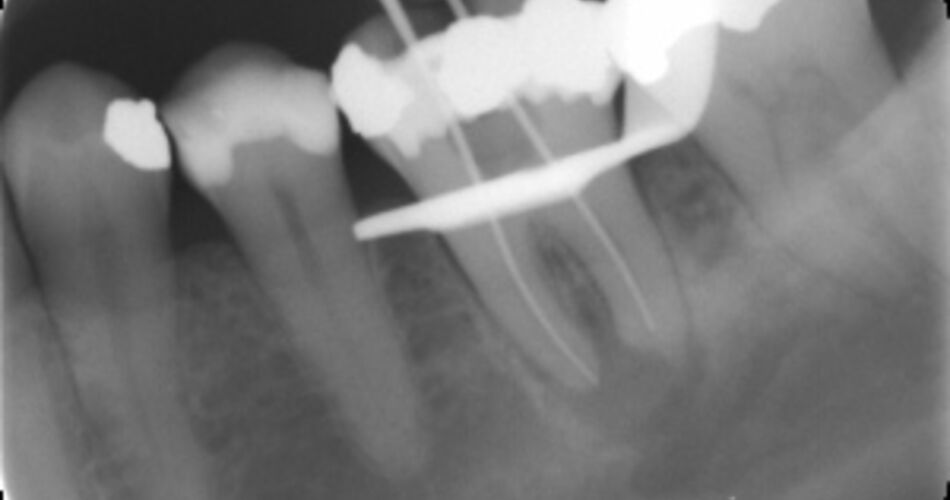

Norsk pasientskadeerstatning (NPE) behandlet til sammen 300 tannlegesaker i 2013. Sakene gjaldt behandling både i privat og offentlig tannhelsetjeneste. Utbetalinger etter feil behandling hos tannleger i privat sektor er nær doblet fra 2012 til 2013. I 2013 ble det utbetalt nesten 10 millioner kroner i erstatning.

Av alle tannlegeklagene dreide 24 % seg om behandling i offentlig tannhelsetjeneste og 76 % gjaldt behandling i privat tannhelsetjeneste. Nytt av året er at en sak gjelder behandling hos tannpleier.

Pasienten fikk medhold på klagen sin i 43 % av tilfellene for tannhelsetjenesten sett under ett. Klager mot tannleger som er rubrisert i gruppen «Tannleger innen oral kirurgi, medisin, protetikk og implantater» var de som sjeldnest førte fram, her ble bare 33 % av klagene tatt til følge. I offentlig tannhelsetjeneste fikk 38 % av klagerne medhold.

Totalt er det behandlet 817 klager på tannbehandling siden NPE startet å behandle tannlegesaker i 2009.